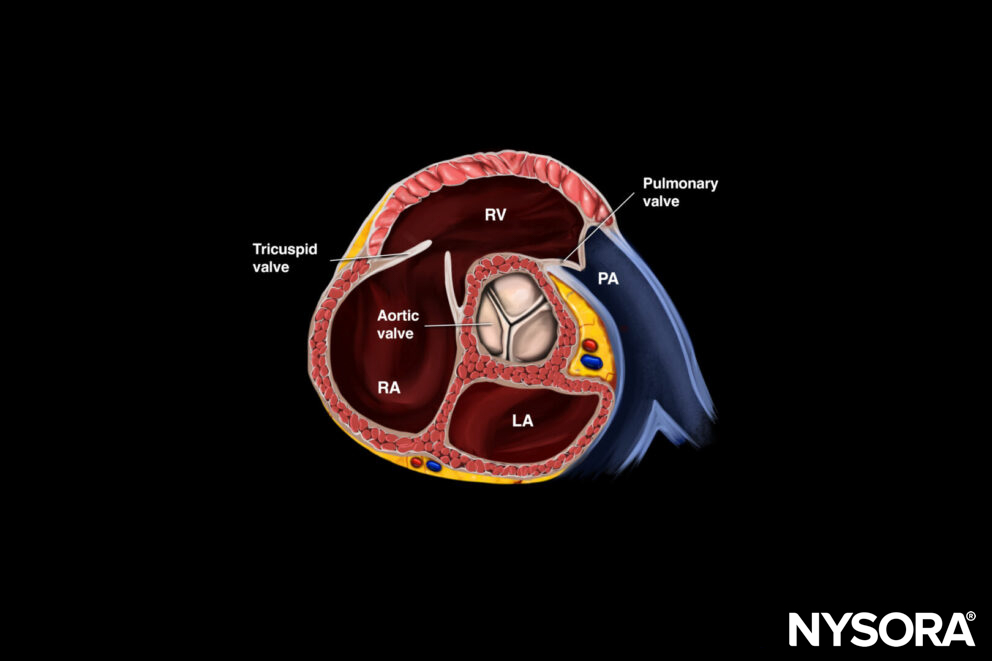

Anatomy of the heart

The heart consists of four chambers (right atrium, right ventricle, left atrium, and left ventricle) and four valves (tricuspid valve, pulmonic valve, mitral valve, and aortic valve).

Functional anatomy of the heart and relevant structures. The blue arrows and vessels represent deoxygenated blood, while the red vessels and arrows represent blood rich in oxygen.